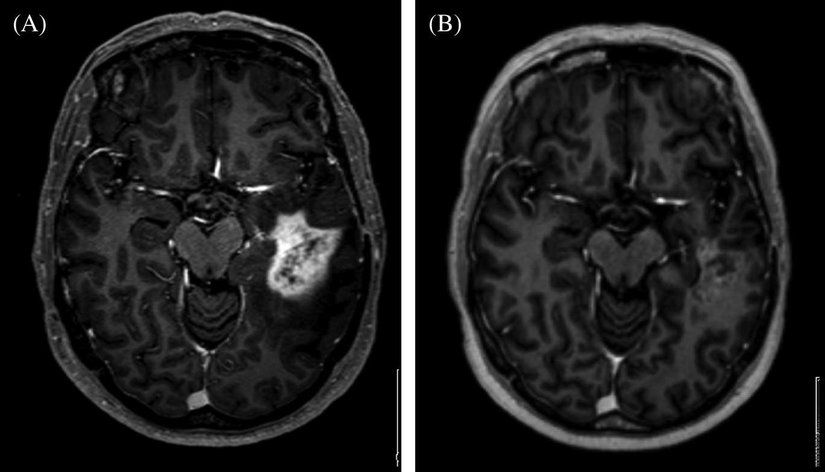

Beyindeki hücrelerini yenilenirken meydana gelen hatalı anormal hücrelerin büyümesi, kolonileşmesi sırasında meydana gelen yapıya “beyin tümörü" denir. Beyin tümörleri doğrudan beyin hücrelerinde ya da vücudun başka organlarından sirayet etmiş kanserli hücreler olabilir. Beyin hücrelerinde meydana gelen tümörlere “primer” beyin tümörü organlardan sirayet etmiş hücrelere “seconder ” ya da metastaz denir. Beyin tümörleri iyi huylu(benign), kötü huylu(malign) olarak ikiye ayrılır.[1], [2], [3], [4]

Beynin kendi hücrelerinde meydana gelen bozuklukların büyük kısmı kötü huylu tümörlerdir, DNA yenileme sürecinde meydana gelen bir hata nedeniyle oluşan hastalıklı hücrelerin toplanmasıyla oluşur tedavisi çoğunlukla ameliyattır, ameliyatla kötü huylu tümörlerin tamamen alınması tümörle beyin dokusu arasında iyi huylu tümörlerdeki gibi bir kapsül veya benzeri bir yapı olmadığından ameliyatla alınan tümörlerin tamamen alınması mümkün değildir bu yüzden ameliyattan sonra tümörün tekrar büyümesi olasıdır, kötü huylu tümörlerin 4 seviyesi vardır 1. ve 2. seviyedeki tümörler düşük seviyeli tümörlerdir ve seyri ve tedavisi 3. Ve 4. Seviyedeki tümörlere göre nispeten daha iyidir 3.(Anaplastik) ve 4. (Glibostroma multiforme) seviyeli tümörler daha yüksek seviyelidir.

Kötü huylu tümörlerin tedavisi genelde ameliyat gerektirir bunun dışında radyoterapi ve kemoterapi gibi tedavi yöntemleri de tümör tedavisinde uygulanabilir. Ameliyattan önce nöronavigasyon ile tümörün yeri tespit edilir nöromonitorizasyon ile hastanın yüz kol ve bacak felci yaşama ihtimalini büyük oranda azaltmaya yarar. Gliolan Boyama Tekniği İle tümör dokusu ile beyin dokusu farklı renklerde gösterek ayırır. Bazı durumlarda beynin motor alanı denilen hassas bölgelerinde hastanın kol ve bacak hareketlerinin beyinde komut edildiği yer gözlemlenerek ameliyat riski azaltılmaktadır bu uygulamaya uyanık kranitonomi denir.